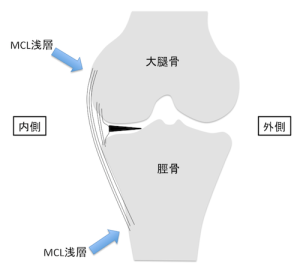

🦵 内側側副靭帯(MCL)損傷とは

内側側副靭帯(MCL)損傷とは、膝関節の内側にある

「内側側副靭帯(Medial Collateral Ligament)」が伸びたり、部分的に断裂

あるいは完全に断裂してしまう外傷です。

MCLは、膝が内側に開く動き(外反ストレス)を防ぎ、関節の安定性を保つ重要な

役割を担っています。特に歩行や走行、方向転換などの日常動作やスポーツ動作において、

膝を安定させるために欠かせない靭帯です。